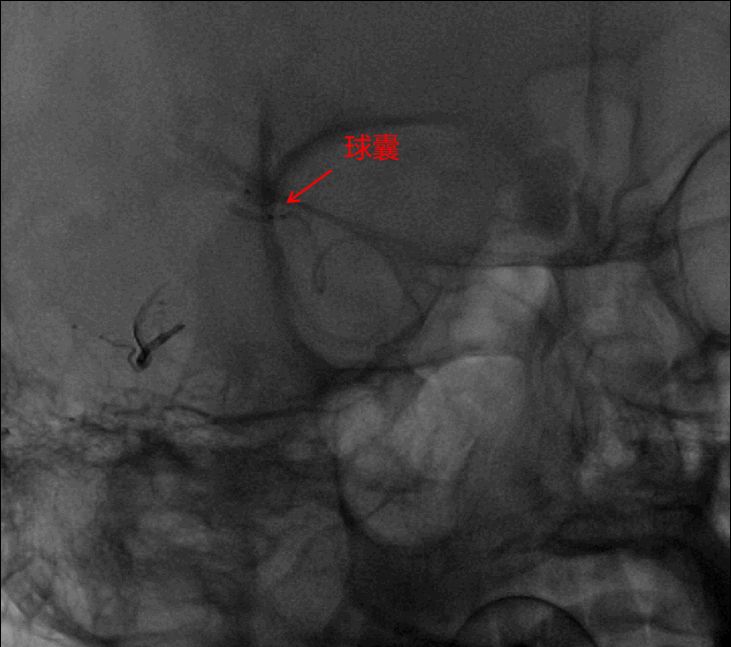

将Scepter C 4*15球囊经颈内动脉超选到大脑中动脉颞支(畸形团主要供血动脉),充盈球囊,阻断动脉端畸形团血流。

经静脉及动脉依次注射ONYX18约4ml,注胶时,球囊的阻断起到了关键作用(高压锅技术)。